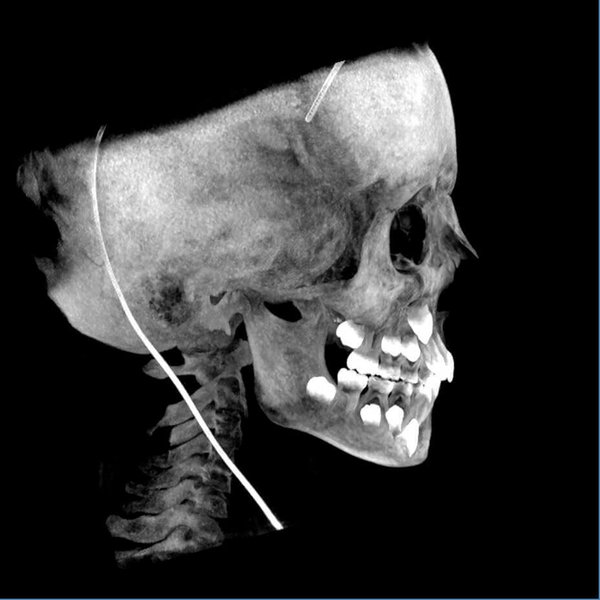

Acquisizione Maxiillofacciale per valutazione chirurgica di paziente con Sindrome di Goldenhar